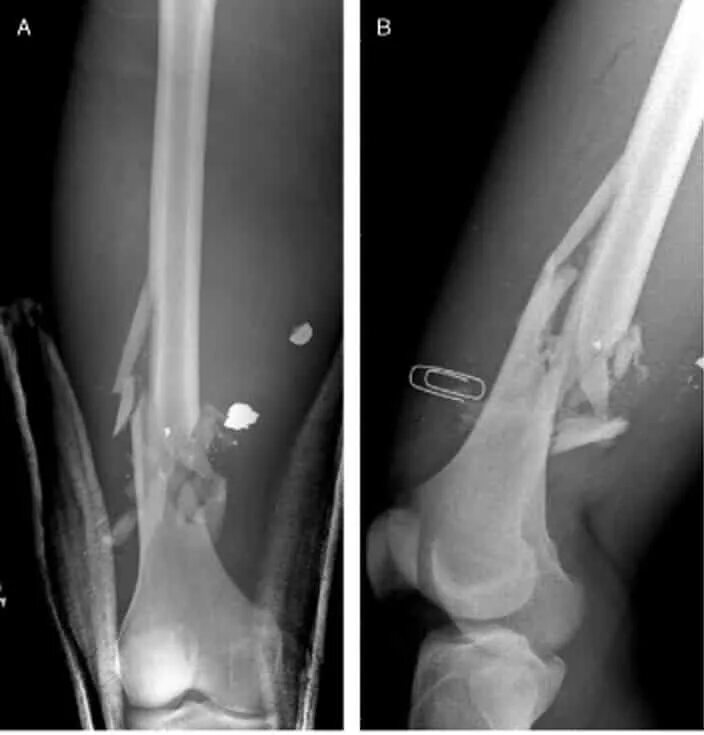

Разрушение мягких тканей